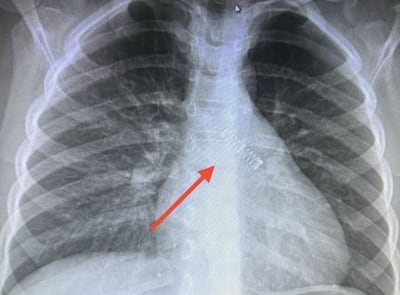

La radiografía reveló la presencia nítida de un resorte de bolígrafo alojado en el bronquio fuente izquierdo.

Debido al tiempo transcurrido desde diciembre, el cuerpo extraño ya presentaba signos de integración con el tejido pulmonar.